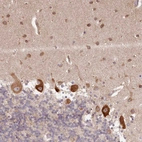

Immunohistochemical staining of human cerebral cortex shows strong cytoplasmic positivity in neurons.